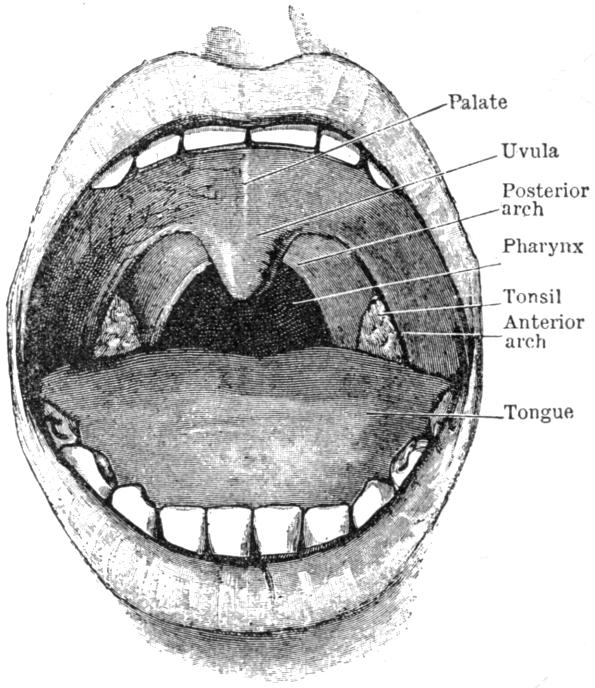

| V. | The Circulation | H 51 |

| VII. | Food and Digestion | H 89 |